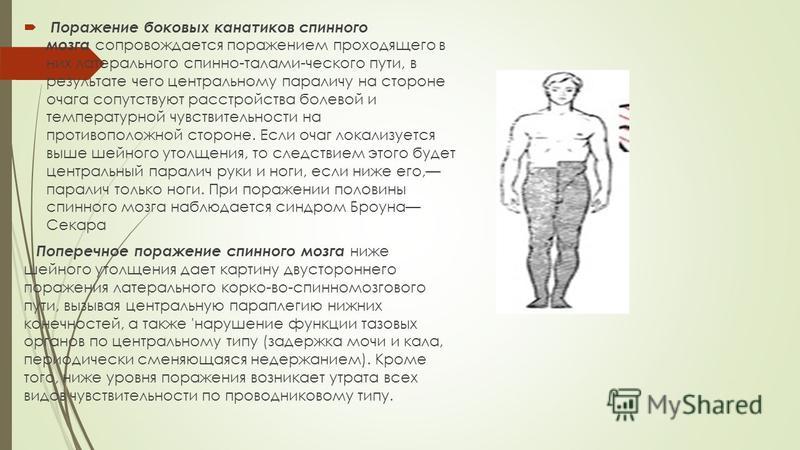

Пирамидная симптоматика в неврологии: ключевые аспекты